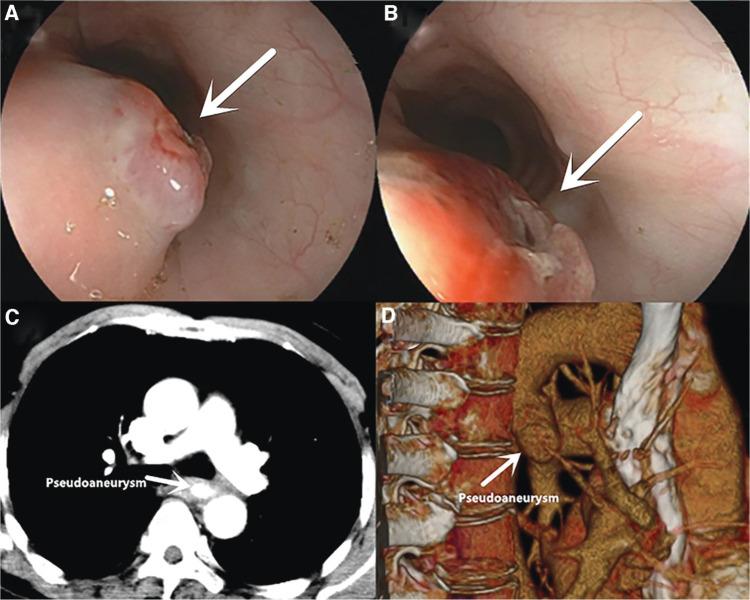

PRIMARY AORTOESOPHAGEAL FISTULA DUE TO ESOPHAGEAL FOREIGN BODY: A CASE REPORT.

https://cdn.ncbi.nlm.nih.gov/pmc/blobs/9b51/8635267/7a68df5f48dd/gastnu-44-458-g001.jpg